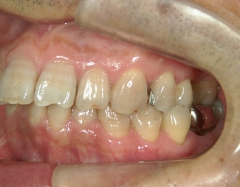

矯正歯科 治療前矯正歯科 治療前

矯正歯科 治療前 右上4番、左右下4番 計3本抜歯し、叢生を改善

no.22_8175_治療前_右.jpgno.22_8175_治療前_正面.jpgno.22_8175_治療前_左.jpg